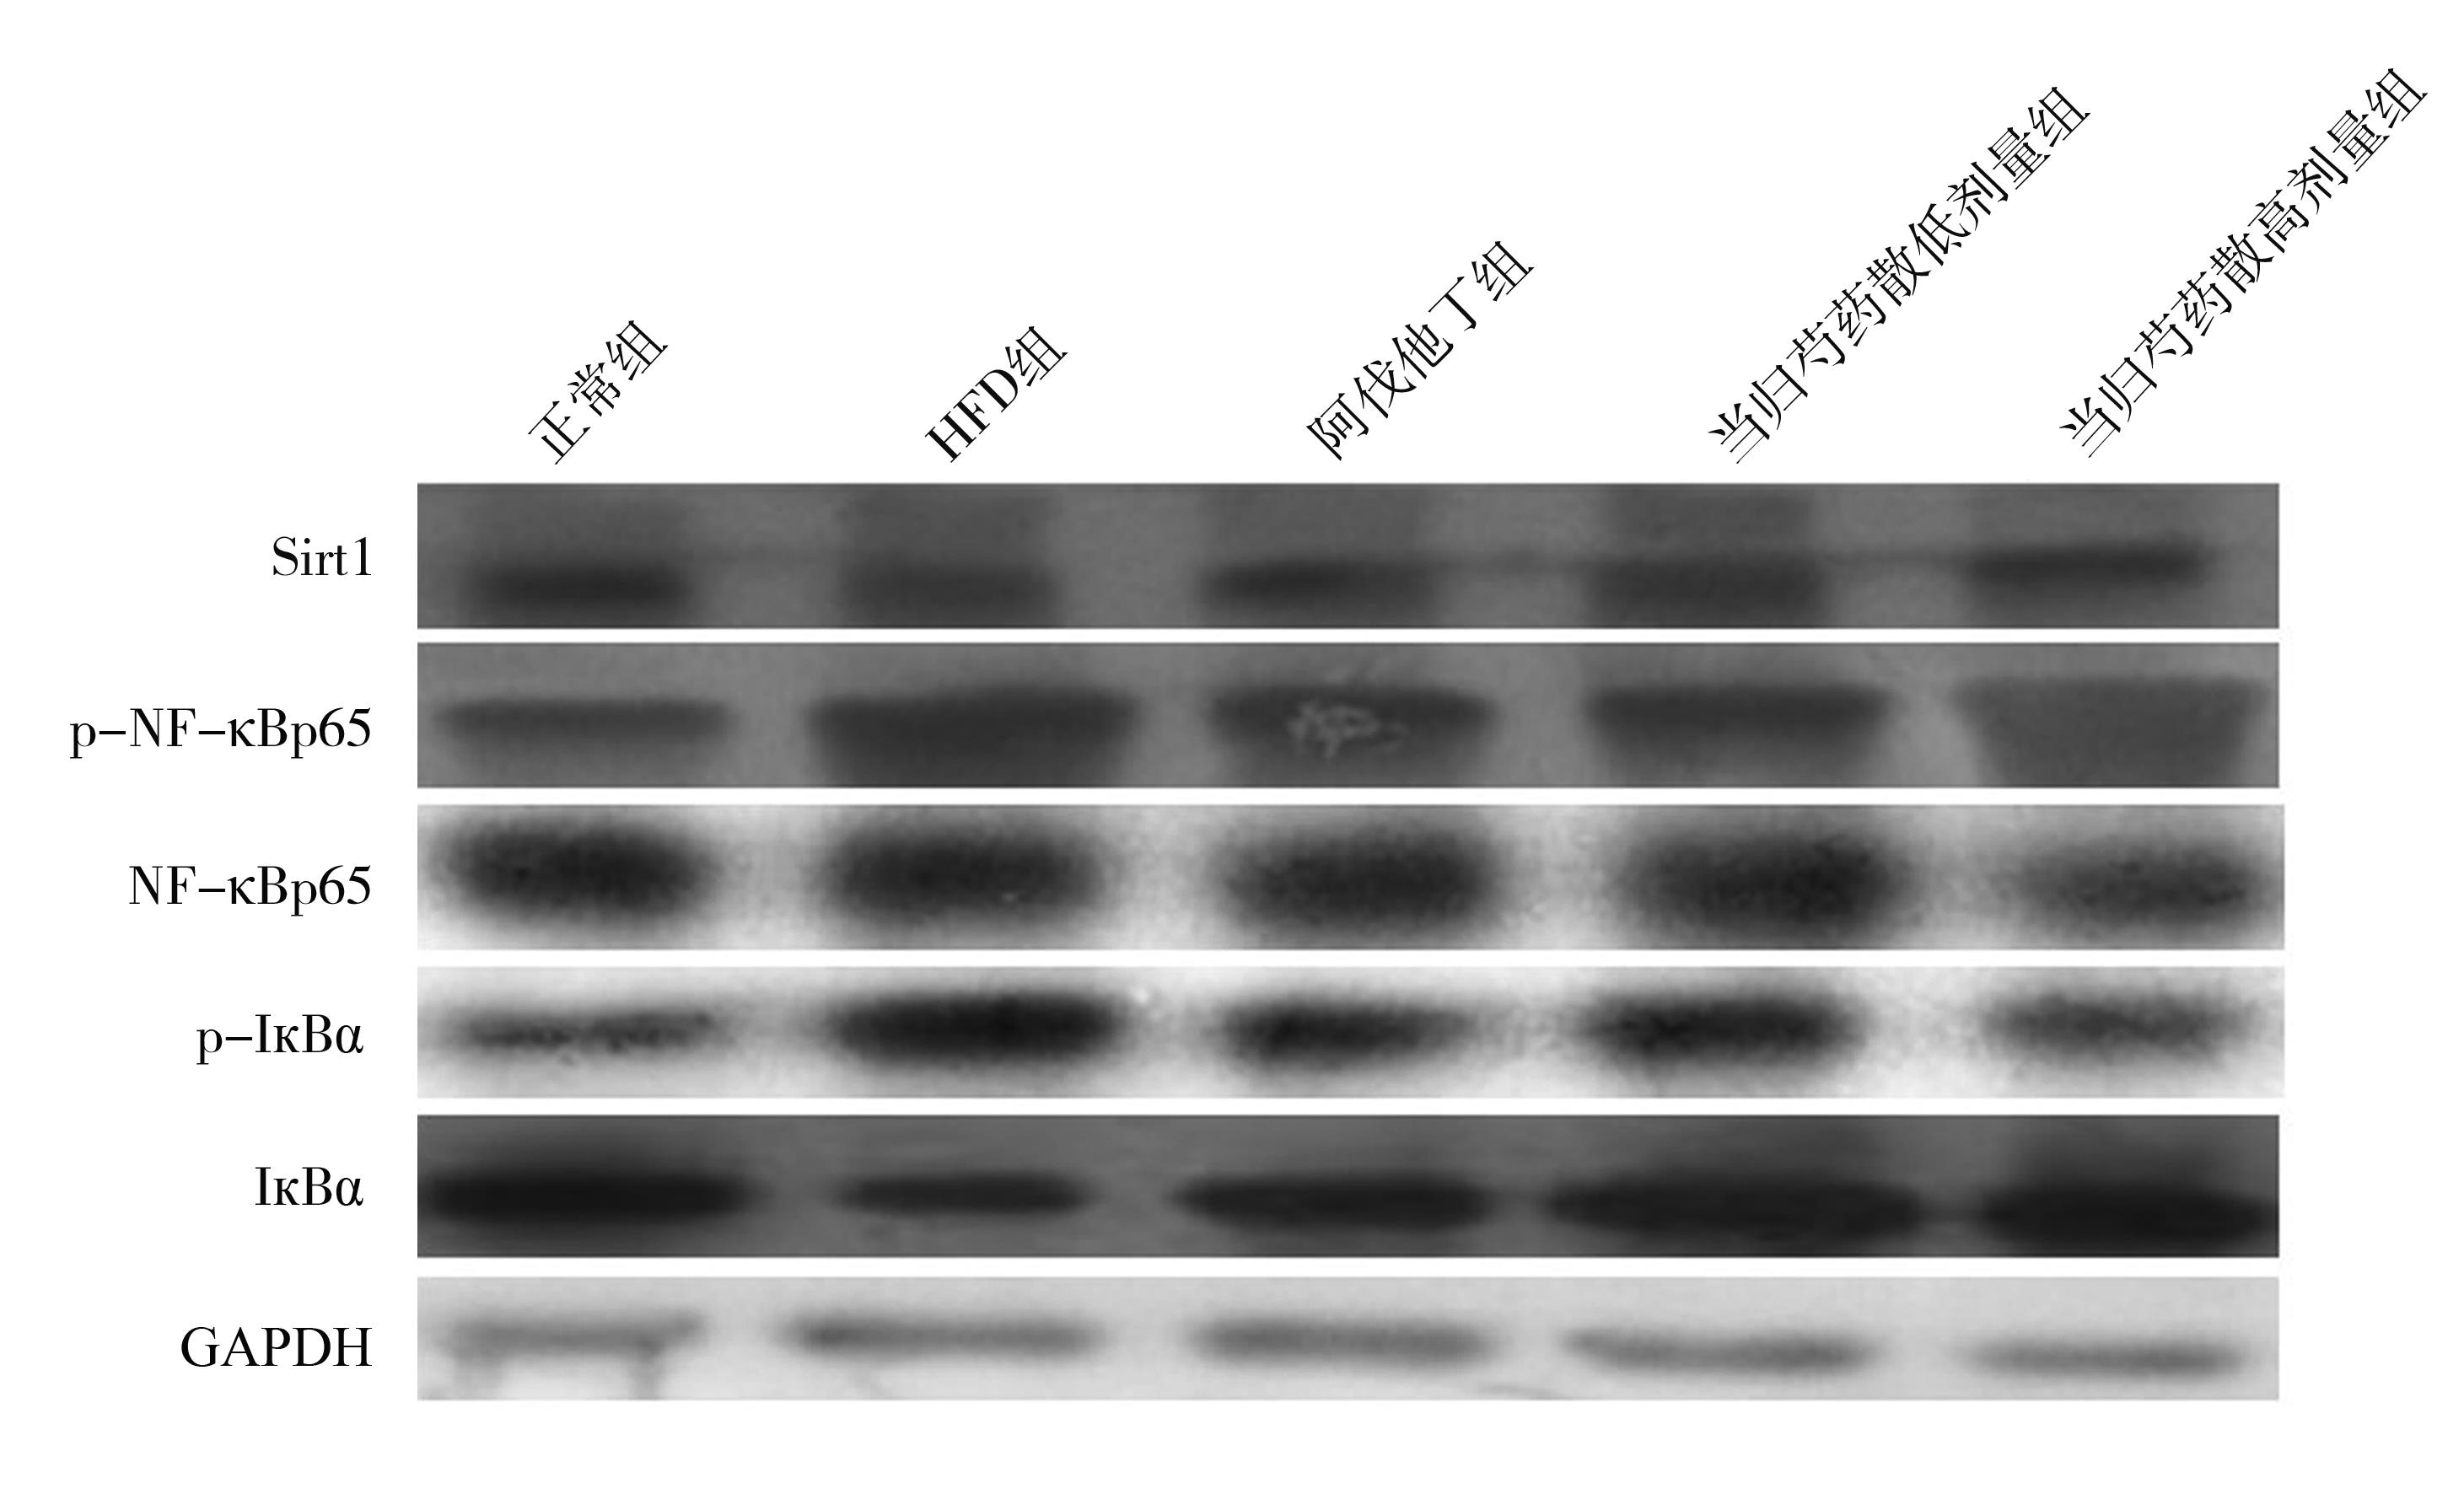

• 当归芍药散通过调节Sirt1/NF-κB信号通路改善高脂饮食诱导大鼠非酒精性脂肪肝炎症反应

2023, 48(6):656-661. DOI: 10.13406/j.cnki.cyxb.003261

摘要 (87) HTML (27) PDF 1.71 M (245) 评论 (0) 收藏

摘要:目的 研究当归芍药散治疗高脂饮食(high-fat diet,HFD)诱导的大鼠非酒精性脂肪性肝病(nonalcoholic fatty liver disease,NAFLD)炎症反应的作用机制。方法 将大鼠随机分为5组:正常组、HFD组、阿伐他丁组、当归芍药散低剂量组、当归芍药散高剂量组。大鼠给予高脂肪饲料(59.3%脂肪饲料)6周,正常组大鼠同时给予正常饲料。从第5周开始,阿伐他丁组大鼠灌胃给予25 mg/kg阿伐他丁2周,当归芍药散低剂量组大鼠灌胃给予12.9 g/kg当归芍药散2周,当归芍药散高剂量组大鼠灌胃给予25.8 g/kg当归芍药散2周,检测大鼠血清丙氨酸氨基转移酶(alanine aminotransferase,ALT)、天冬氨酸氨基转移酶(aspartate aminotransferase,AST)、甘油三酯(triglyceride,TG)、胆固醇(cholesterol,TC)、血清细胞因子水平。同时检测大鼠肝脏沉默信息调节因子1(sirtuin 1,Sirt1)/核转录因子-κB(nuclear factor kappa-B,NF-κB)信号通路蛋白表达。结果 与模型组比较,当归芍药散能显著降低血清ALT、AST、TG、TC、血清细胞因子水平,改善肝脏组织病理学改变。此外,显著增加大鼠肝脏Sirt1表达,抑制肝脏NF-κB蛋白表达。结论 当归芍药散通过Sirt1/NF-κB通路治疗HFD大鼠NAFLD。

• 0+1

• 1+1

• 2+1

• 3+1

• 4+1

• 5+1

• 6+1